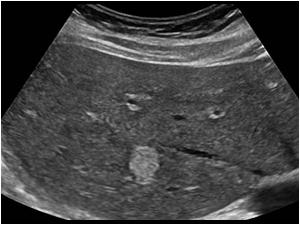

Polycystic liver disease

Multiple cysts with posterior acoustic enhancement, consistent with polycystic liver disease.

What is this pathology?